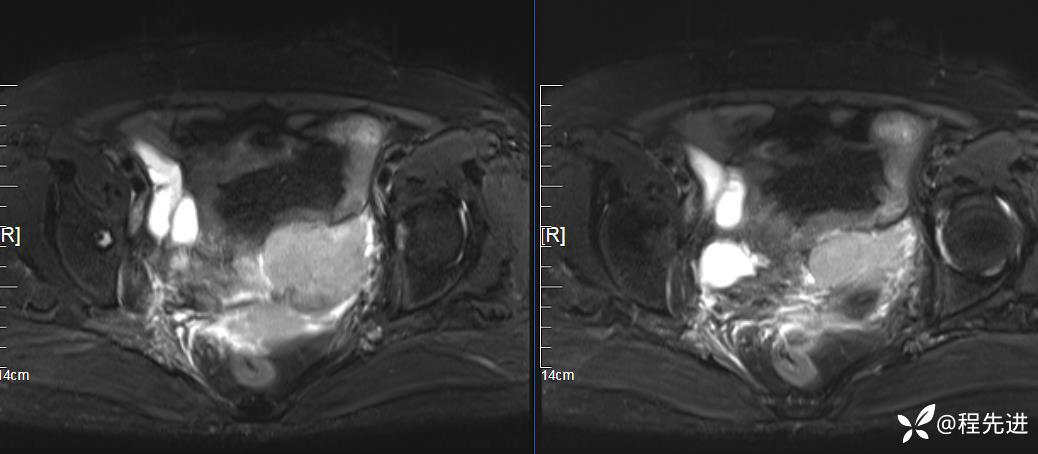

MRI平扫: